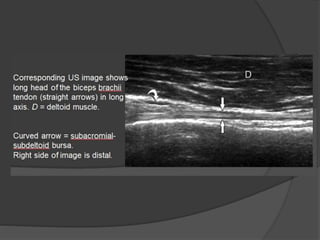

The transducer is then turned 90° to visualize the biceps

tendon in long axis.

Transducer pressure distally is usually needed to aim the

ultrasound beam cephalad and perpendicular to the biceps

tendon, which will appear hyperechoic and fibrillar.

If the biceps brachii tendon is oblique to the sound beam, it

will appear hypoechoic from anisotropy.